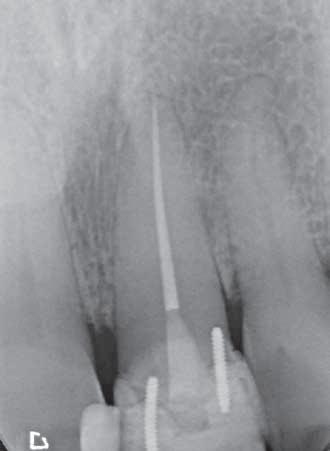

The patient was originally referred concerning this tooth in 2022. A CBCT scan was recommended because the clinical assessment revealed no pathological findings – however, a small lateral lesion was suspected. A periapical x-ray revealed severe calcification of the tooth (Figure 1).

The patient returned in May 2024 reporting a history of slight discomfort

from the tooth. In the intervening two years, the patient’s dentist had applied a composite build-up, secured using two pins, making the UL1 heavily restored. A new CBCT scan showed severe calcification of the root canal, and a lateral radiolucency mid-root on the distal aspect (marked with red arrow) (Figure 2).

3: Periapical X-ray to check orientation of file